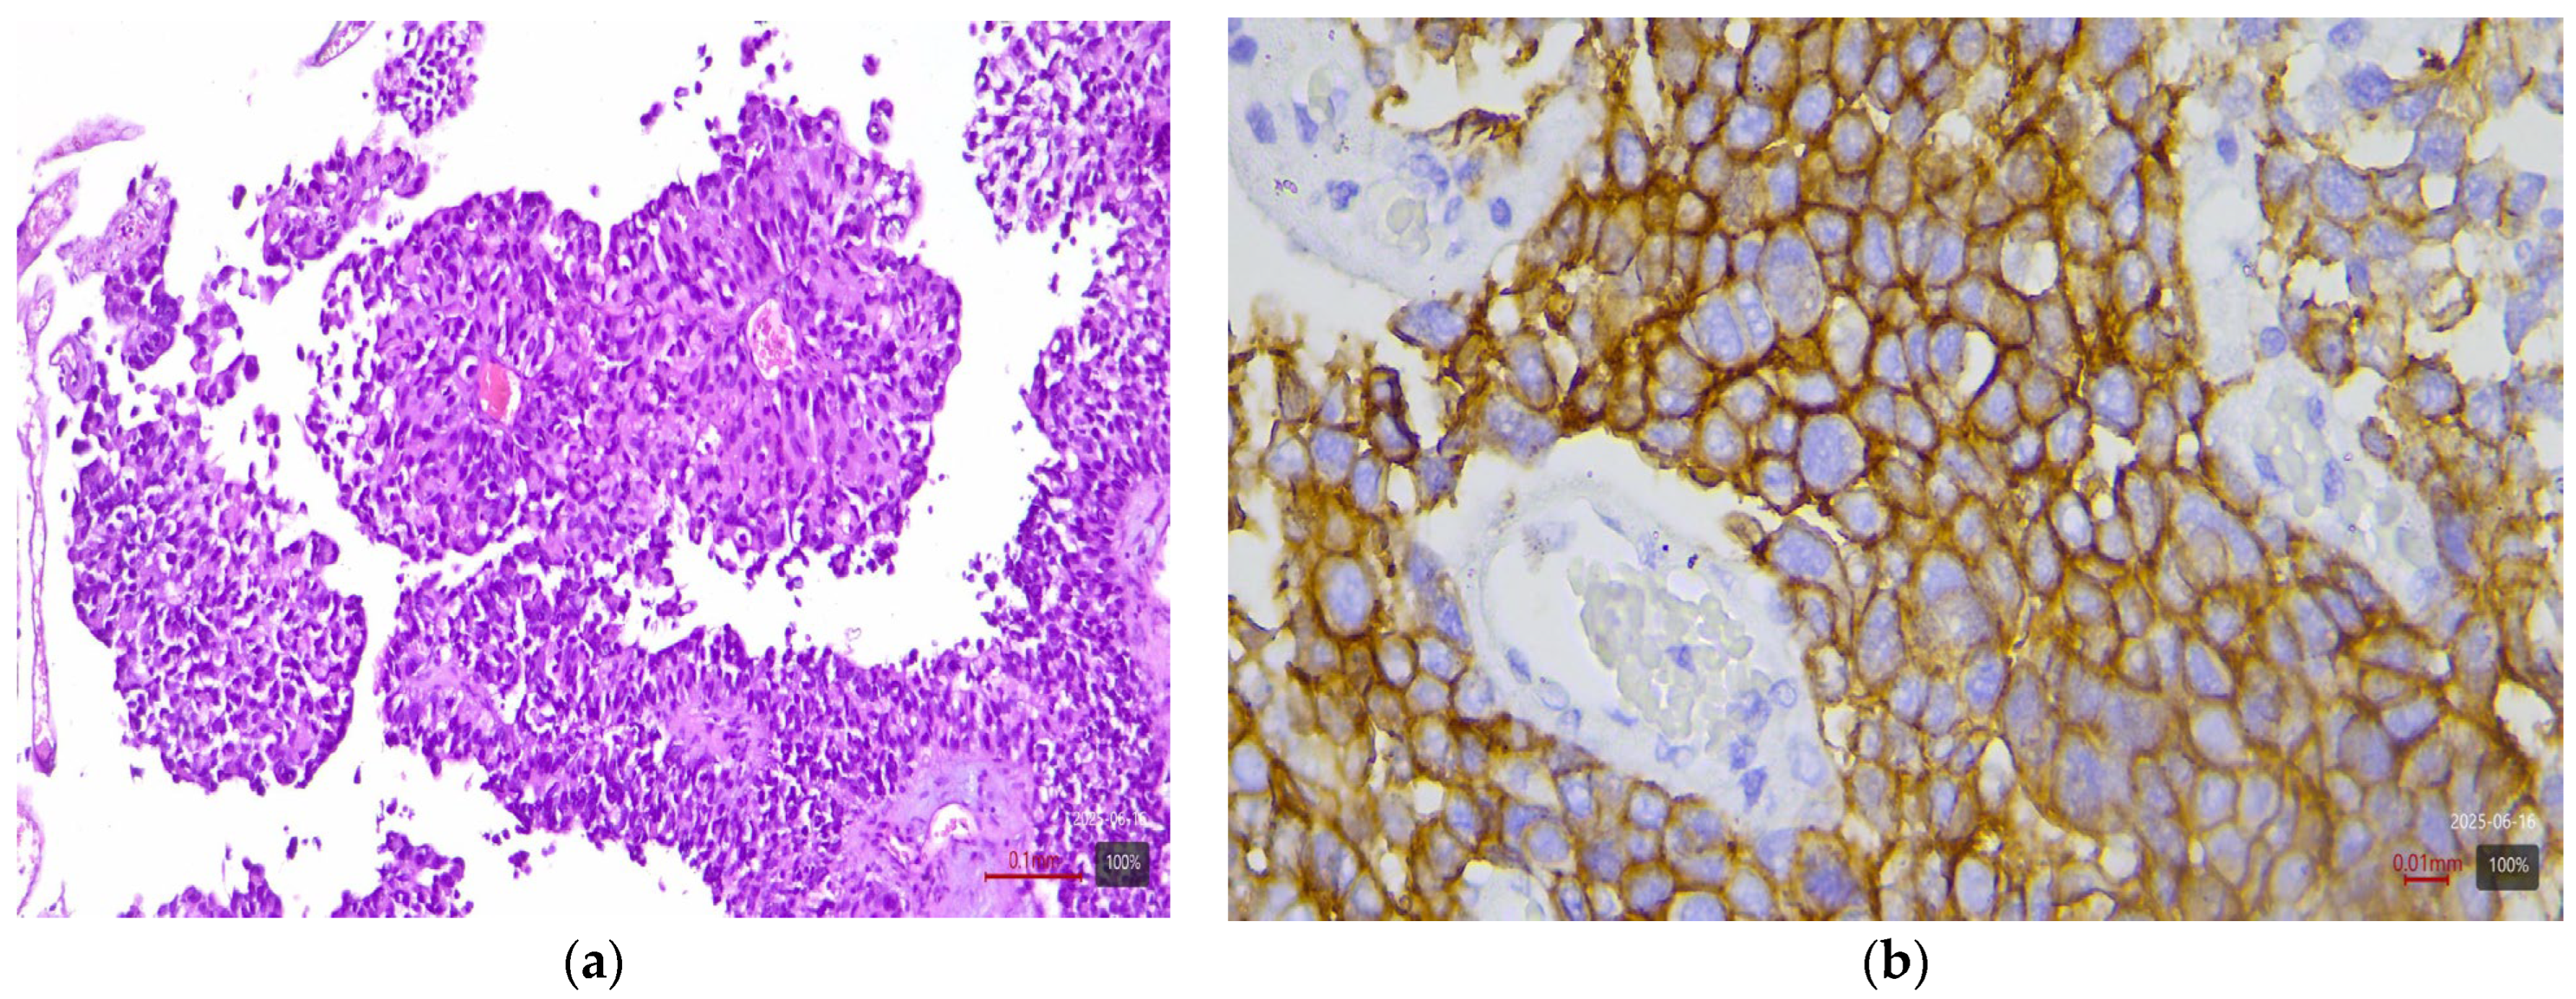

2.3. Histological and Molecular Subtyping of Tumors

2.4. Immunohistochemical Study of HER2

2.5. Interpretation of HER2 Status